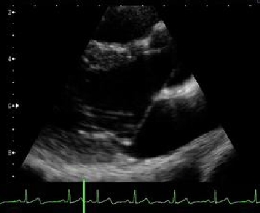

Mitral Valve Prolapse

- この症例は、動悸、胸痛等の症状はなく、心雑音の異常もなく、

- 心電図にも異常所見がありませんでした。

- 身体所見で、Marfan 症候群が疑われたために、心エコー図検査を行いました。

- Marfan症候群は、僧帽弁逸脱症を合併することがある疾患であります。